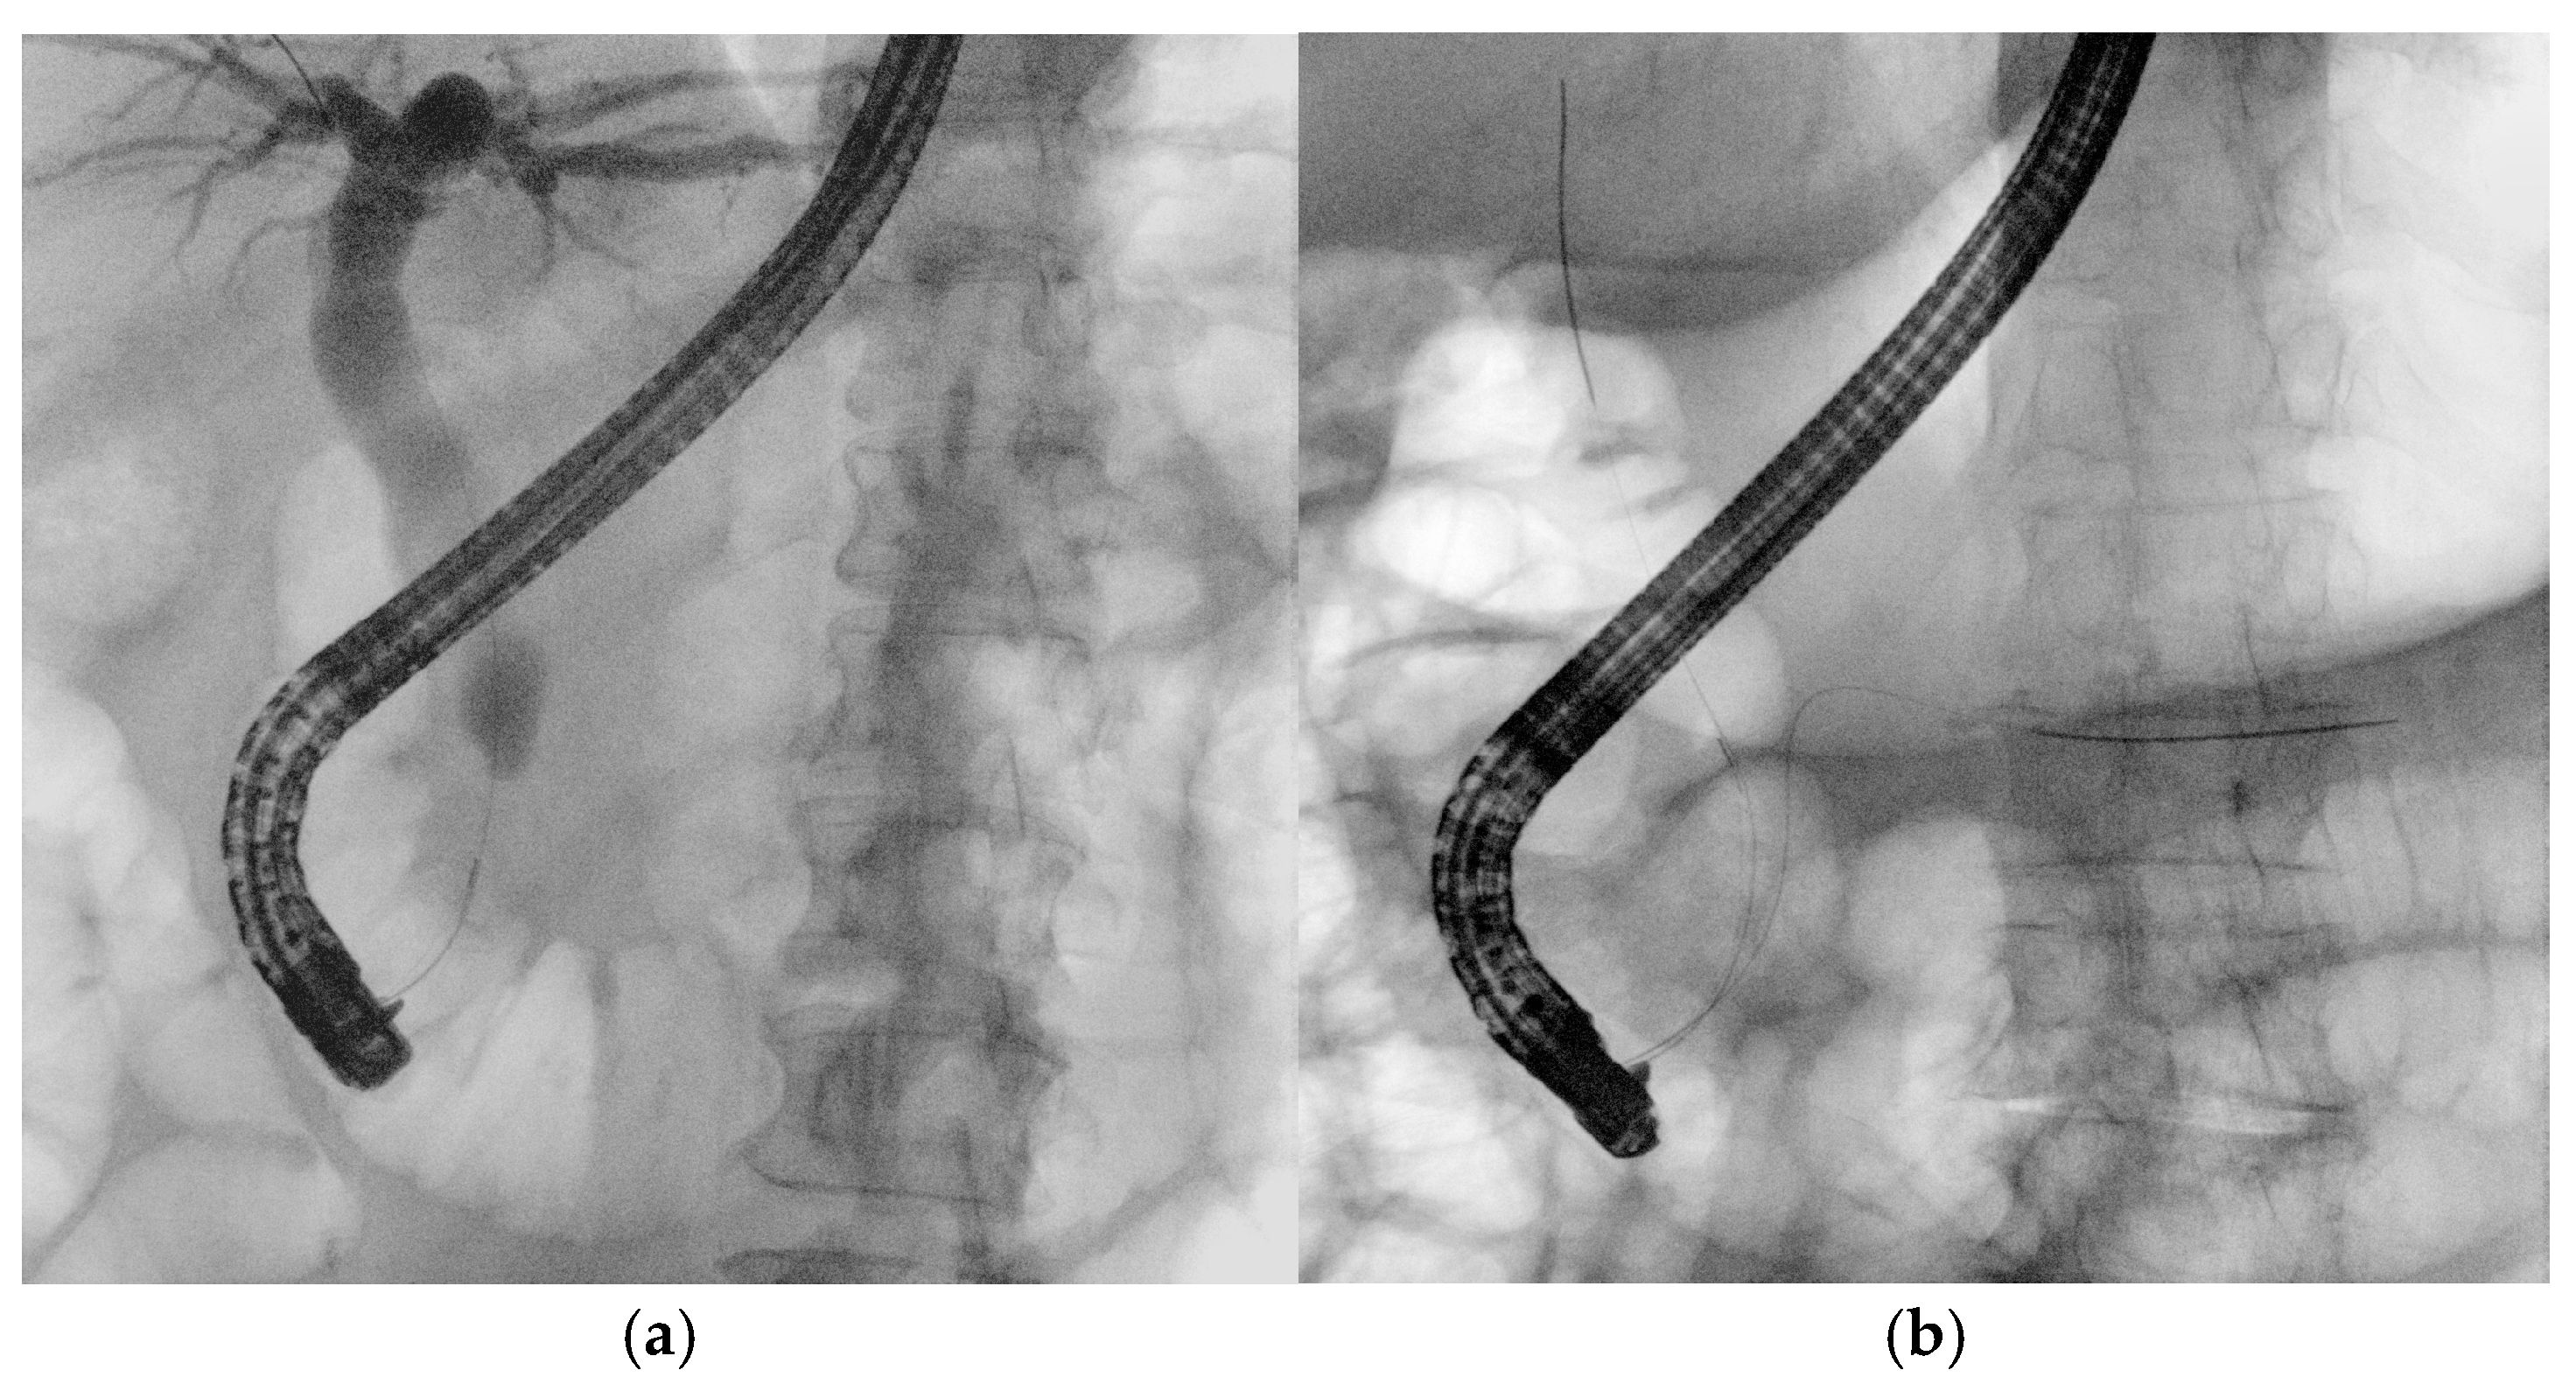

3.2. Pancreatic Duct Cannulation

Selective pancreatic duct cannulation is indicated for various pancreatic disorders, such as idiopathic recurrent acute pancreatitis, chronic pancreatitis, pancreatic ductal injuries, fistula formation, and sphincter of Oddi dysfunction (Figure 5) [22,28]. Pancreatic duct access can be challenging either due to the smaller caliber of the duct or the presence of pathological conditions such as stenosis, stones, or altered anatomy. Typically, smaller-caliber guidewires (0.025- or 0.018-inch) and fully hydrophilic guidewires are used. In very difficult cases, an advanced technique, known as either the reverse double-guidewire cannulation or the bile duct guidewire indwelling method according to different authors, has been described. In this technique, the first guidewire is placed into the biliary duct, which helps keep the papilla open and stabilized, pulls the septum superiorly, and straightens the pancreatic duct, facilitating its cannulation with a second guidewire. This approach can also be useful in cases of parapapillary diverticulum with a deviated papilla and increased papillary mobility, as well as in patients with a tortuous and elongated papillary sphincter muscle [29]. Notably, a case report describes the successful use of an uneven double-lumen cannula (0.025- and 0.035-inch lumens) for the same purpose [30]. Access to the main pancreatic duct (MPD) through the major papilla is sometimes impossible due to pancreas divisum, a distortion of Wirsung’s duct, or other anatomical variations, necessitating minor papilla cannulation [31]. In this setting, experts recommend WGC using small-caliber guidewires (0.018- and 0.021-inch), with or without contrast injection, followed by a standard pull-type sphincterotomy or a needle-knife sphincterotomy over a stent [22]. When the deep cannulation of the dorsal duct with a pull-sphincterotome fails, wire-assisted access sphincterotomy is an alternative technique. After successful deep cannulation with a guidewire, the sphincterotome is exchanged for a needle-knife, which is advanced alongside the wire; then, the minor papilla is incised using the wire as an anatomic guide. Compared to freehand precut sphincterotomy, it ensures early and stable wire access. Additionally, unlike needle-knife sphincterotomy over a stent, it allows for further interventions without requiring stent removal [32].

Figure 5. Guidewire-assisted pancreatic cannulation followed by contrast injection showing a dilated and tortuous main pancreatic duct in the context of chronic pancreatitis.